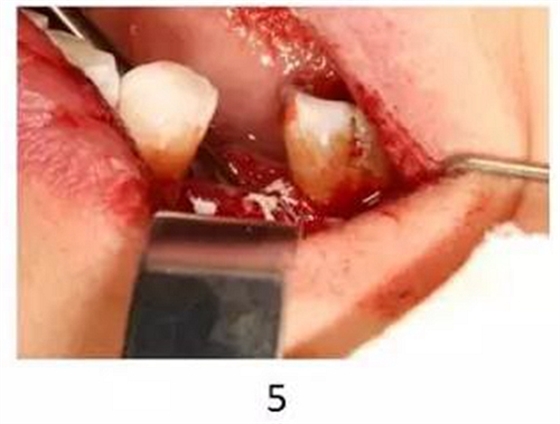

圖2-5-8 Er,Cr:YSGG輔助種植體周圍炎手術(shù)治療(GBR)

1.Er,Cr:YSGG輔助種植體表面去污

2. Er,Cr:YSGG輔助去除種植體周圍感染肉芽組織和骨組織

3. 種植體表面覆蓋自體骨

4. 植入骨代用品

5. 覆蓋屏障膜